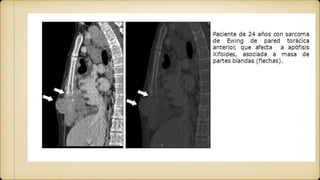

• 27.

TC de un condrosarcoma involucrandoel esternón y clavículas, demostrando destrucción ósea y calcificación moteada dentro del tumor